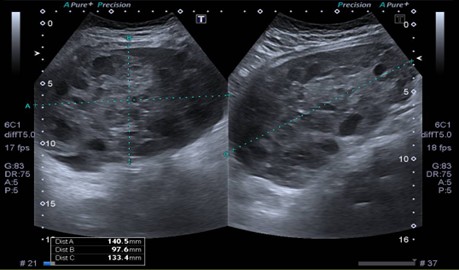

Se realizó nueva ecografía en el hospital que informa masa en topografía centro abdominal, de aproximadamente 14 x 9.7 x 13.3 cm (ver Imagen 1). El útero mide 5,5 cm en su diámetro máximo. No se logran identificar ovarios derecho o izquierdo. Se solicita radiografía de mano izquierda para valorar edad ósea la cual, según el atlas de carpograma de Oxford 2011, evidencia edad ósea de 10 años para cronológica de 8 y 3 meses.

Figura 1. Ecografía abdominal del ingreso. Se visualiza voluminosa masa en topografía centro abdominal, sólido-quística a predominio sólido de 14 x 9.7 x 1.3 cm.